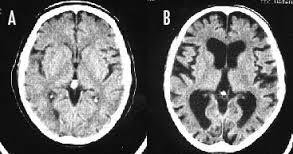

>>4341 大脳皮質が薄くなり認知機能が落ちる 『たばこ脳』 ※写真は左Aが正常の脳、右Bが喫煙者の脳です。 左の脳と比べて右の脳は隙間だらけになってしまっています。

--- 「喫煙者の脳」やはり異変が起きていた(石田雅彦) - Yahoo!ニュース ---

タバコを吸うと脳がすっきりするのは真っ赤な嘘だ。研究によれば喫煙者の脳では明らかに異常が起きている。認知機能も低下し、大脳皮質が元に戻るのには25年もかかる。一刻も早くタバコなど止めたほうがいい。